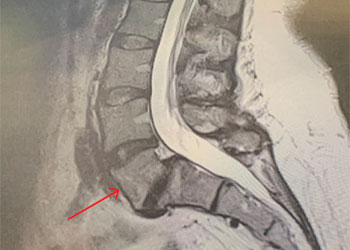

This is a 46-year-old woman who presented with a 9 mm right-sided pituitary adenoma with a recent diagnosis of Cushing’s Disease. For two years she noticed some swelling of her body. The swelling was much more noticeable recently. She had pronounced swelling of her face, body, and legs. She was also recently diagnosed with hypertension and diabetes. She also had some recent impairment of her memory and thought processes. Her endocrine testing was consistent with Cushing’s Disease, that is, a pituitary source of her high systemic cortisol levels.